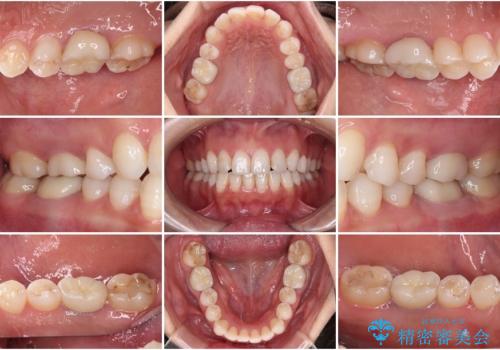

[ セラミック・インプラント全顎治療 ] 長年悩まされている歯の治療にケリをつけたい

![[ セラミック・インプラント全顎治療 ] 長年悩まされている歯の治療にケリをつけたいの症例 治療後](https://seimitsushinbi.jp/wp/wp-content/uploads/2022/01/f4f9ee9ff7018c558de74748d97a4667-500x350.jpg?v=1642042445)